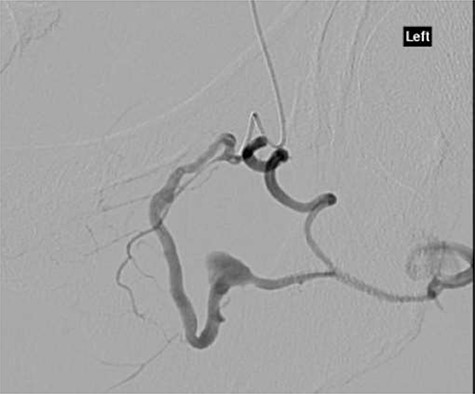

CT angiography showed multiple hypertrophied branches of the left internal iliac artery with heavy collateralisation to the territory of occluded left common femoral artery. Pathological dilatation of the collateral branch of the left obturator artery was identified as source of bleeding and embolized (Fig. 2). A further source of bleeding from a collateral muscular branch of the internal iliac artery was also embolized (Fig. 3).

CT angiography with dye showing dilatation of collateral branch of left obturator artery.